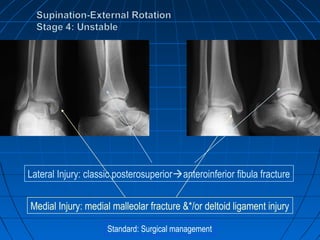

Supination-External RotationSupination-External Rotation

Accounts for 40 to 75% of

Malleolar fractures.

Stage 1- AITFL disruption,

Stage 2- Spiral # of Fibula,

Stage 3- PITFL disruption or

PM #,

Stage 4-Deltoid Ligament

disruption or transverse #

of MM

Standard: Closed management

Lateral Injury: classic posterosuperioranteroinferior fibula fracture

Medial Injury: Stability maintained

Medial Injury: medial malleolar fracture &*/or deltoid ligament injury

Standard: Surgical management